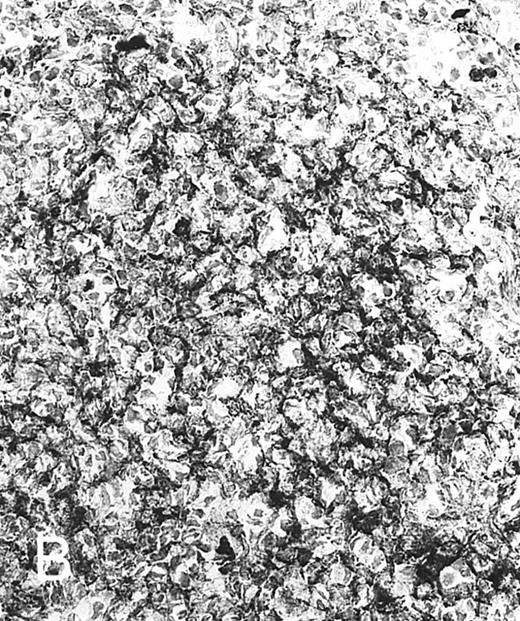

Expression of TGF-β and TGF-β receptor II in tonsillar lymphoid follicle. (A) Immunostain of TGF-β. There is the reticular and dotted positive stain in the apical and basal light zones but not the other follicular zones. MZ, mantle zone; LZ, light zone; DZ, dark zone. Counterstained with methyl green. Original magnification × 132. (B) Immunostain of TGF-βR II. There is the reticular expression in the apical light zone. OZ, outer zone; ALZ, apical light zone; BLZ, basal light zone; DZ, dark zone. Counterstained with methyl green. Original magnification × 100. (C) Immunocytochemical single staining (red color) of TGF-β on an isolated FDC. Original magnification × 1,280. (D) Double staining of TGF-β and R4/23 on the same FDC. There is a positive signal in the cytoplasm of FDC (brown). Counterstained with hematoxylin. Original magnification × 1,280. (E) In situ hybridization of TGF-β cDNA in the ALZ. Dendritic-shaped cells heavily labeled (arrows). Scattered lymphocytes are also stained (arrowheads). Uncounterstained. Original magnification × 860. (F) In situ hybridization of a TGF-βR II oligonucleotide in the ALZ. Many dendritic-shaped cells are strongly positive. Uncounterstained. Original magnification × 400.

TGF-β and TGF-β Receptor II

Immunohistochemically, the ALZ but not the other follicular zones was positive in the reticular meshwork and dotted patterns for TGF-β and TGF-βR II (Tables 3 and 4 and Fig 1A and B). Immunocytochemically, FDCs isolated with MACS were single-positive for TGF-β in their cytoplasm (Fig 1C) and double-positive for TGF-β and R4/23 (Fig 1D). Less frequently, lymphocytes isolated with MACS were positive for TGF-β (<1%). In situ hybridization using a cDNA probe for TGF-β showed the reticular and dotted patterns only in the ALZ labeling cells such as dendritic-shaped cells and lymphocytes and the scattered pattern labeling vascular walls within the whole LF (Table 5 and Fig 1E). In situ hybridization using an oligonucleotide probe for TGF-βRII showed only the reticular pattern in the ALZ labeling dendritic-shaped cells (Fig 1F). Vascular walls within the whole LF were also reacted. Follicular lymphocytes were negative. RT-PCR of samples obtained from the whole tonsillar sample as well as the GC and EGC showed a single-positive band of TGF-β (161 bp; Table 6 and Fig 2A).